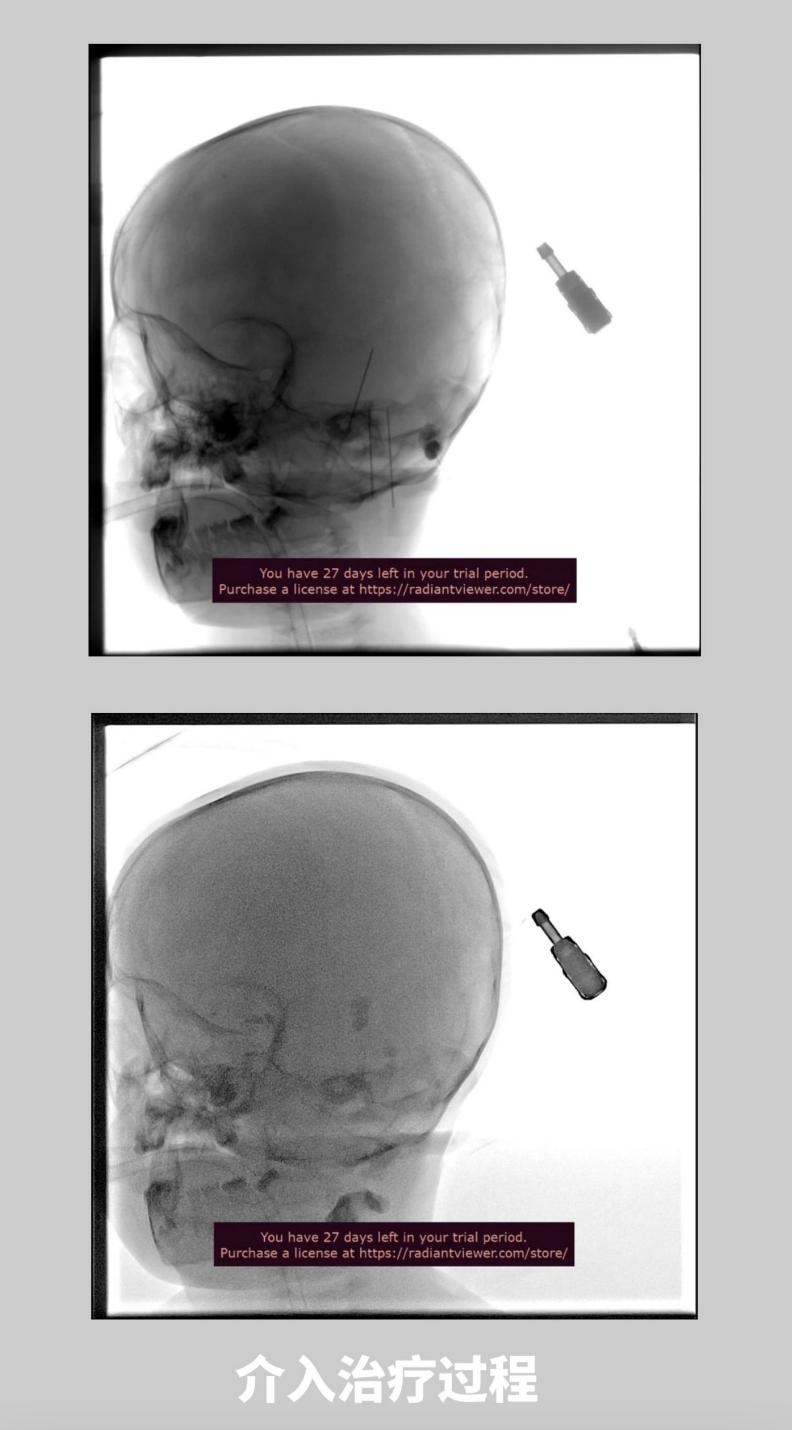

孩子入院后,第二天即接受介入硬化治疗。消毒面部皮肤,在超声及DSA引导下穿刺肿物,成功后用注射器抽出淋巴管液,在DSA透视监视下经皮进行硬化治疗,完成后摄片,显示药液在瘤腔内沉积。手术结束,术中顺利。